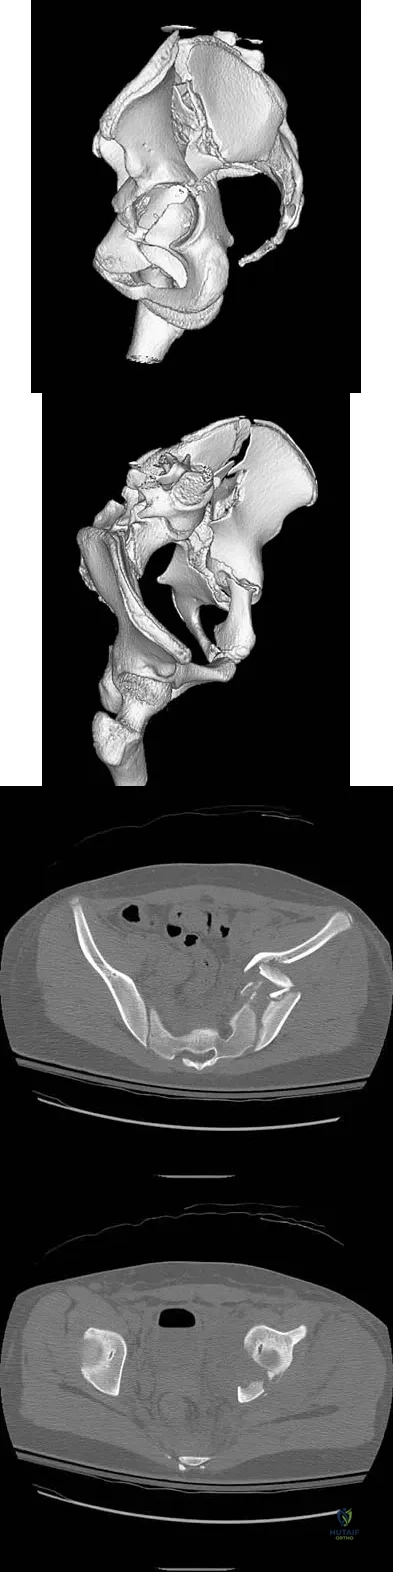

Question 52

A 13-year-old girl was riding on an all-terrain vehicle when the driver struck a tree. She sustained the injury shown in Figures 45a through 45d. This injury is best described as what type of acetabular fracture pattern?

Explanation